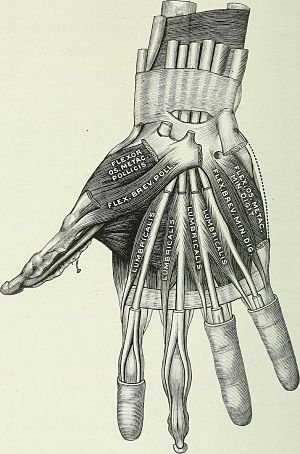

El músculo flexor corto del dedo pulgar forma parte de la eminencia tenar junto con otros tres músculos. Este grupo muscular se ubica en la base del dedo pulgar y se encargan de flexionar y mover el dedo pulgar hacia adentro, para realizar el movimiento de oposición del pulgar o pinza.

Se encuentra ubicado en posición medial e inferior al músculo abductor corto del pulgar y por encima del oponente del pulgar.

Consta de dos vientres musculares llamados superficial y profundo, que tienen orígenes diferentes en los huesos del carpo.

El músculo flexor corto del pulgar se encarga de los movimientos de flexión del pulgar tanto en su base como en su articulación interfalángica.

Su contracción lleva el dedo pulgar hacia adentro y hacia adelante. Con este movimiento colabora con el músculo oponente del pulgar y con el aductor para realizar una de las principales funciones de la mano humana, que es aproximar el pulgar al resto de los dedos.

Esto se conoce como pulgar opuesto o pinza, y es una característica fundamental que diferencia la mano de los hombres de la de los primates, ya que estos son incapaces de realizar este movimiento.